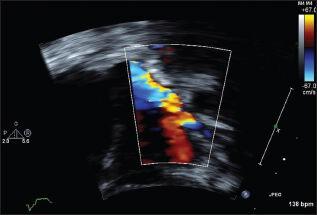

This is a case report of a patient with Trisomy 21 with Ebstein anomaly, a ventricular septal defect, and acquired pulmonary vein stenosis; a rare combination, diagnosed during a routine neonatal examination.

这是一份关于一名患有21三体综合征合并埃布斯坦畸形、室间隔缺损和后天性肺静脉狭窄患者的病例报告,这种罕见的组合在常规新生儿检查中被诊断出来。